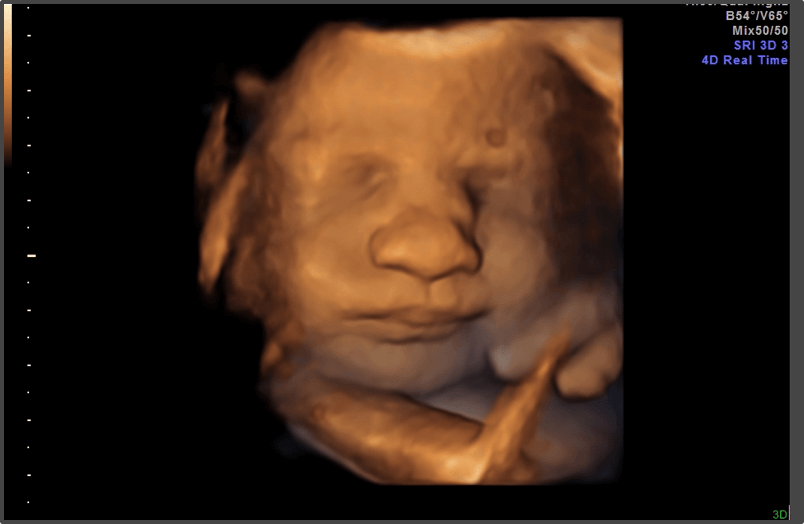

Your baby is the size of a zucchini.

Approx Baby Weight: 1.3kg

Approx Baby Size: 39.9 cm

Baby Development

The baby’s organs are continuing to mature and it is gaining weight.